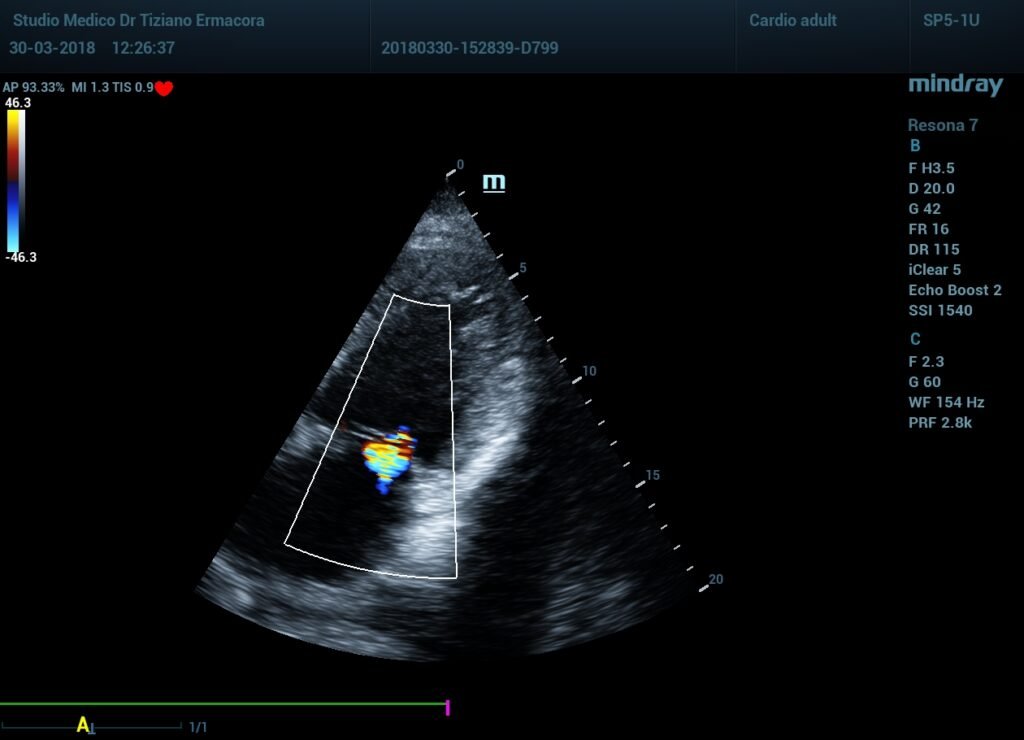

Insufficenza cardiaca

Insufficenza cardiaca, all\’esame ecografico già solo visivamente senza tanti calcoli si evidenza una ridotta contrattilità…